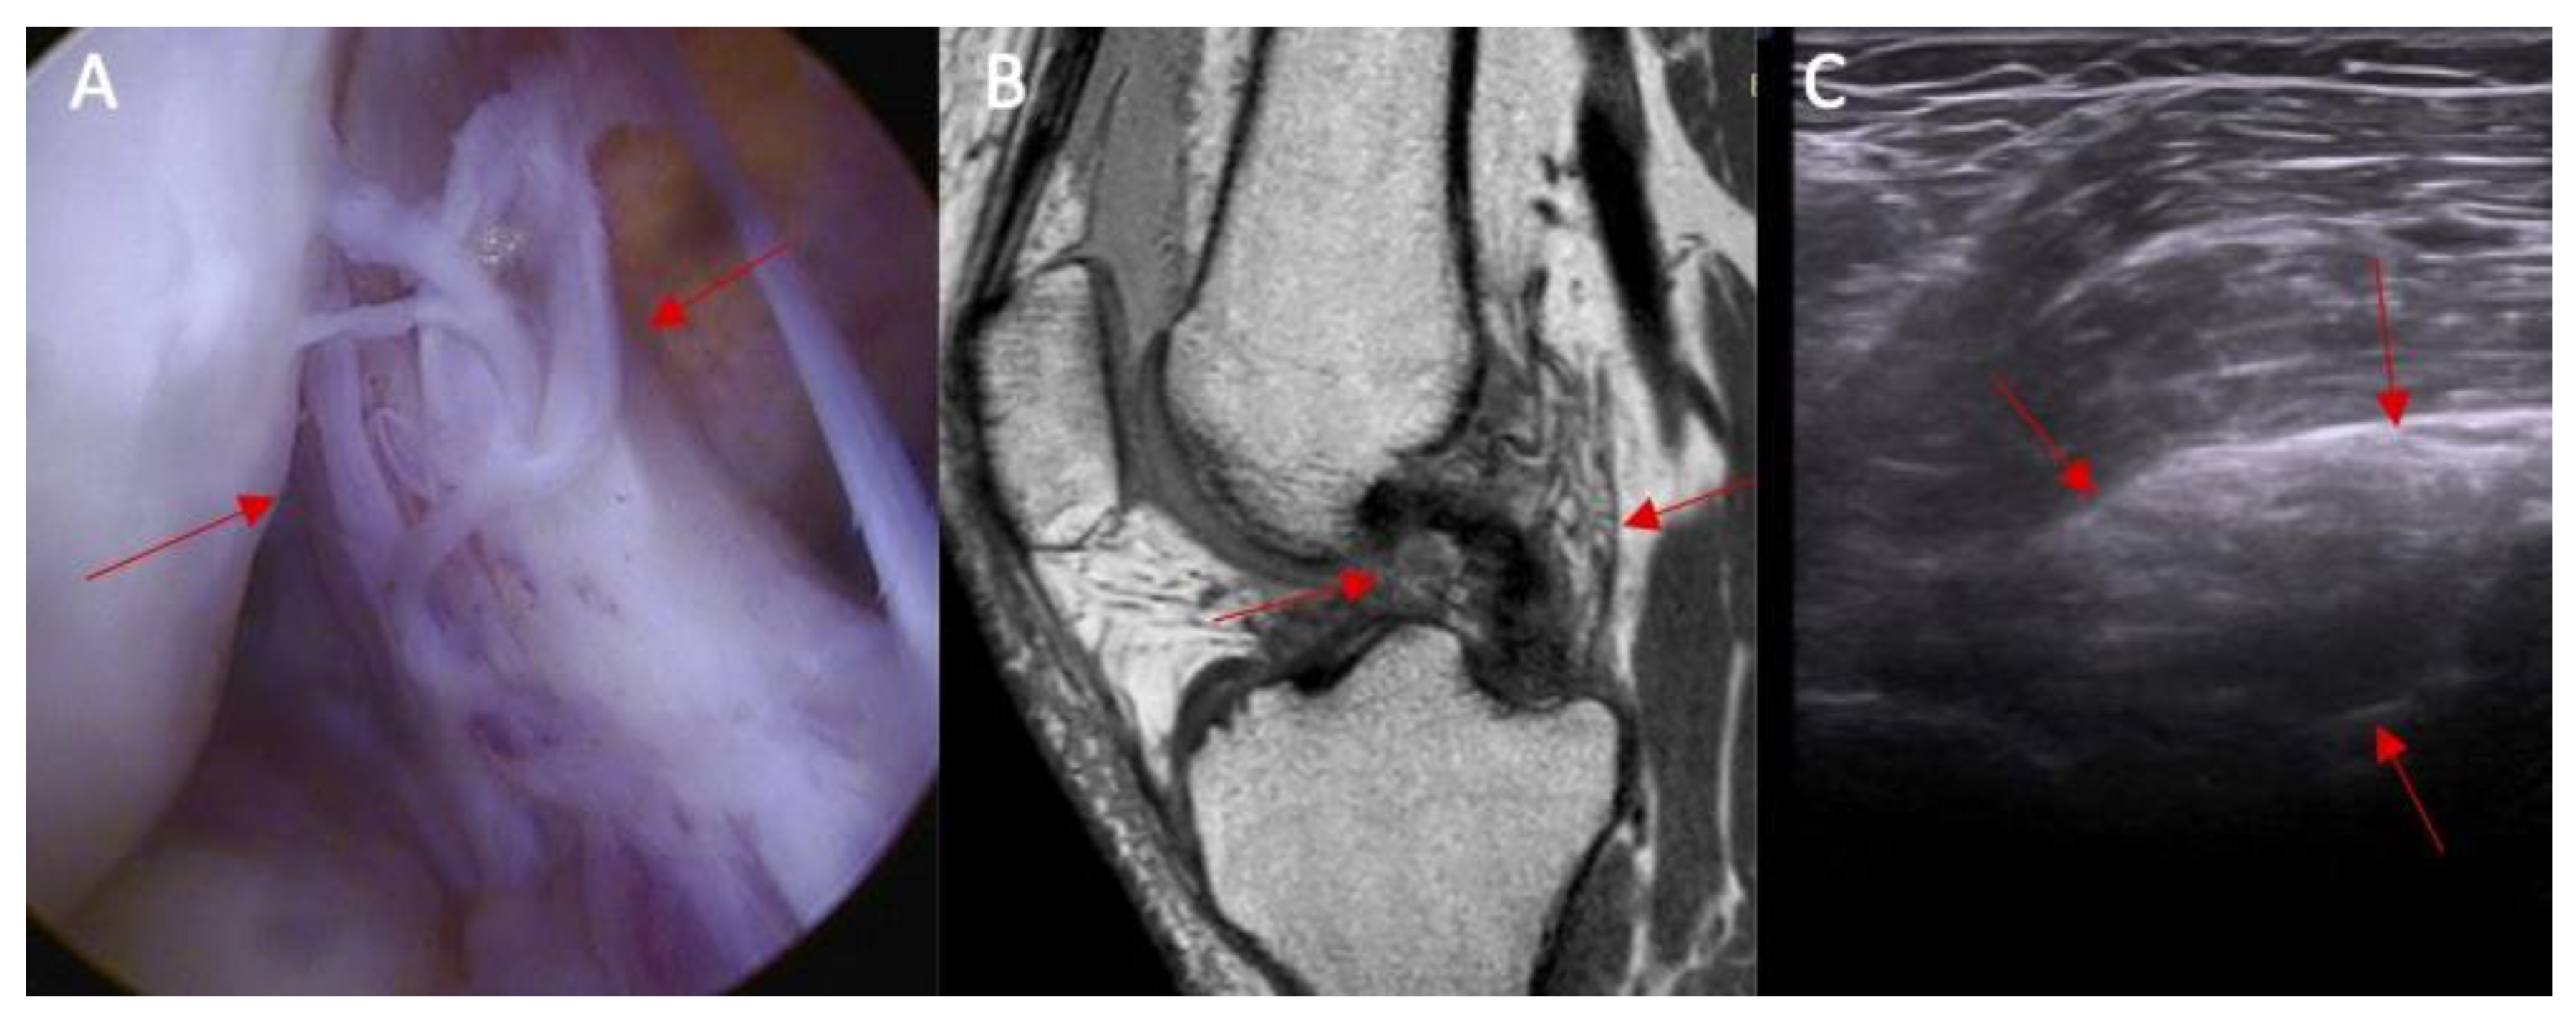

Swelling of the ACL intact to femur condyle was more common in patients with an ACL injury than in those without an ACL injury (83% vs. 0%, respectively, and p < 0.0001) (Figure 5). OR = incalculable.

Figure 5.

The proximal attached (marked with arrows) view of the ACL tear with edema. (A) arthroscopy view; (B) MRI view; and (C) ultrasound view—swelling of the ACL proximal attached to lateral femoral condyle.